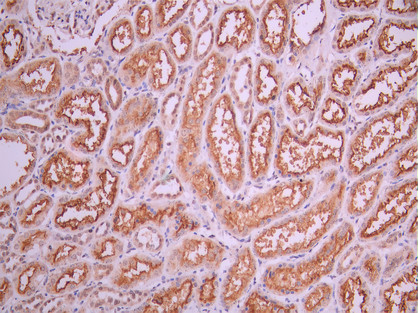

IHC image of CSB-RA121260A0HU diluted at 1:100 and staining in paraffin-embedded human kidney tissue performed on a Leica BondTM system. After dewaxing and hydration, antigen retrieval was mediated by high pressure in a citrate buffer (pH 6.0). Section was blocked with 10% normal goat serum 30min at RT. Then primary antibody (1% BSA) was incubated at 4°C overnight. The primary is detected by a Goat anti-rabbit polymer IgG labeled by HRP and visualized using 0.05% DAB.

IHC image of CSB-RA121260A0HU diluted at 1:100 and staining in paraffin-embedded human liver cancer performed on a Leica BondTM system. After dewaxing and hydration, antigen retrieval was mediated by high pressure in a citrate buffer (pH 6.0). Section was blocked with 10% normal goat serum 30min at RT. Then primary antibody (1% BSA) was incubated at 4°C overnight. The primary is detected by a Goat anti-rabbit polymer IgG labeled by HRP and visualized using 0.05% DAB.